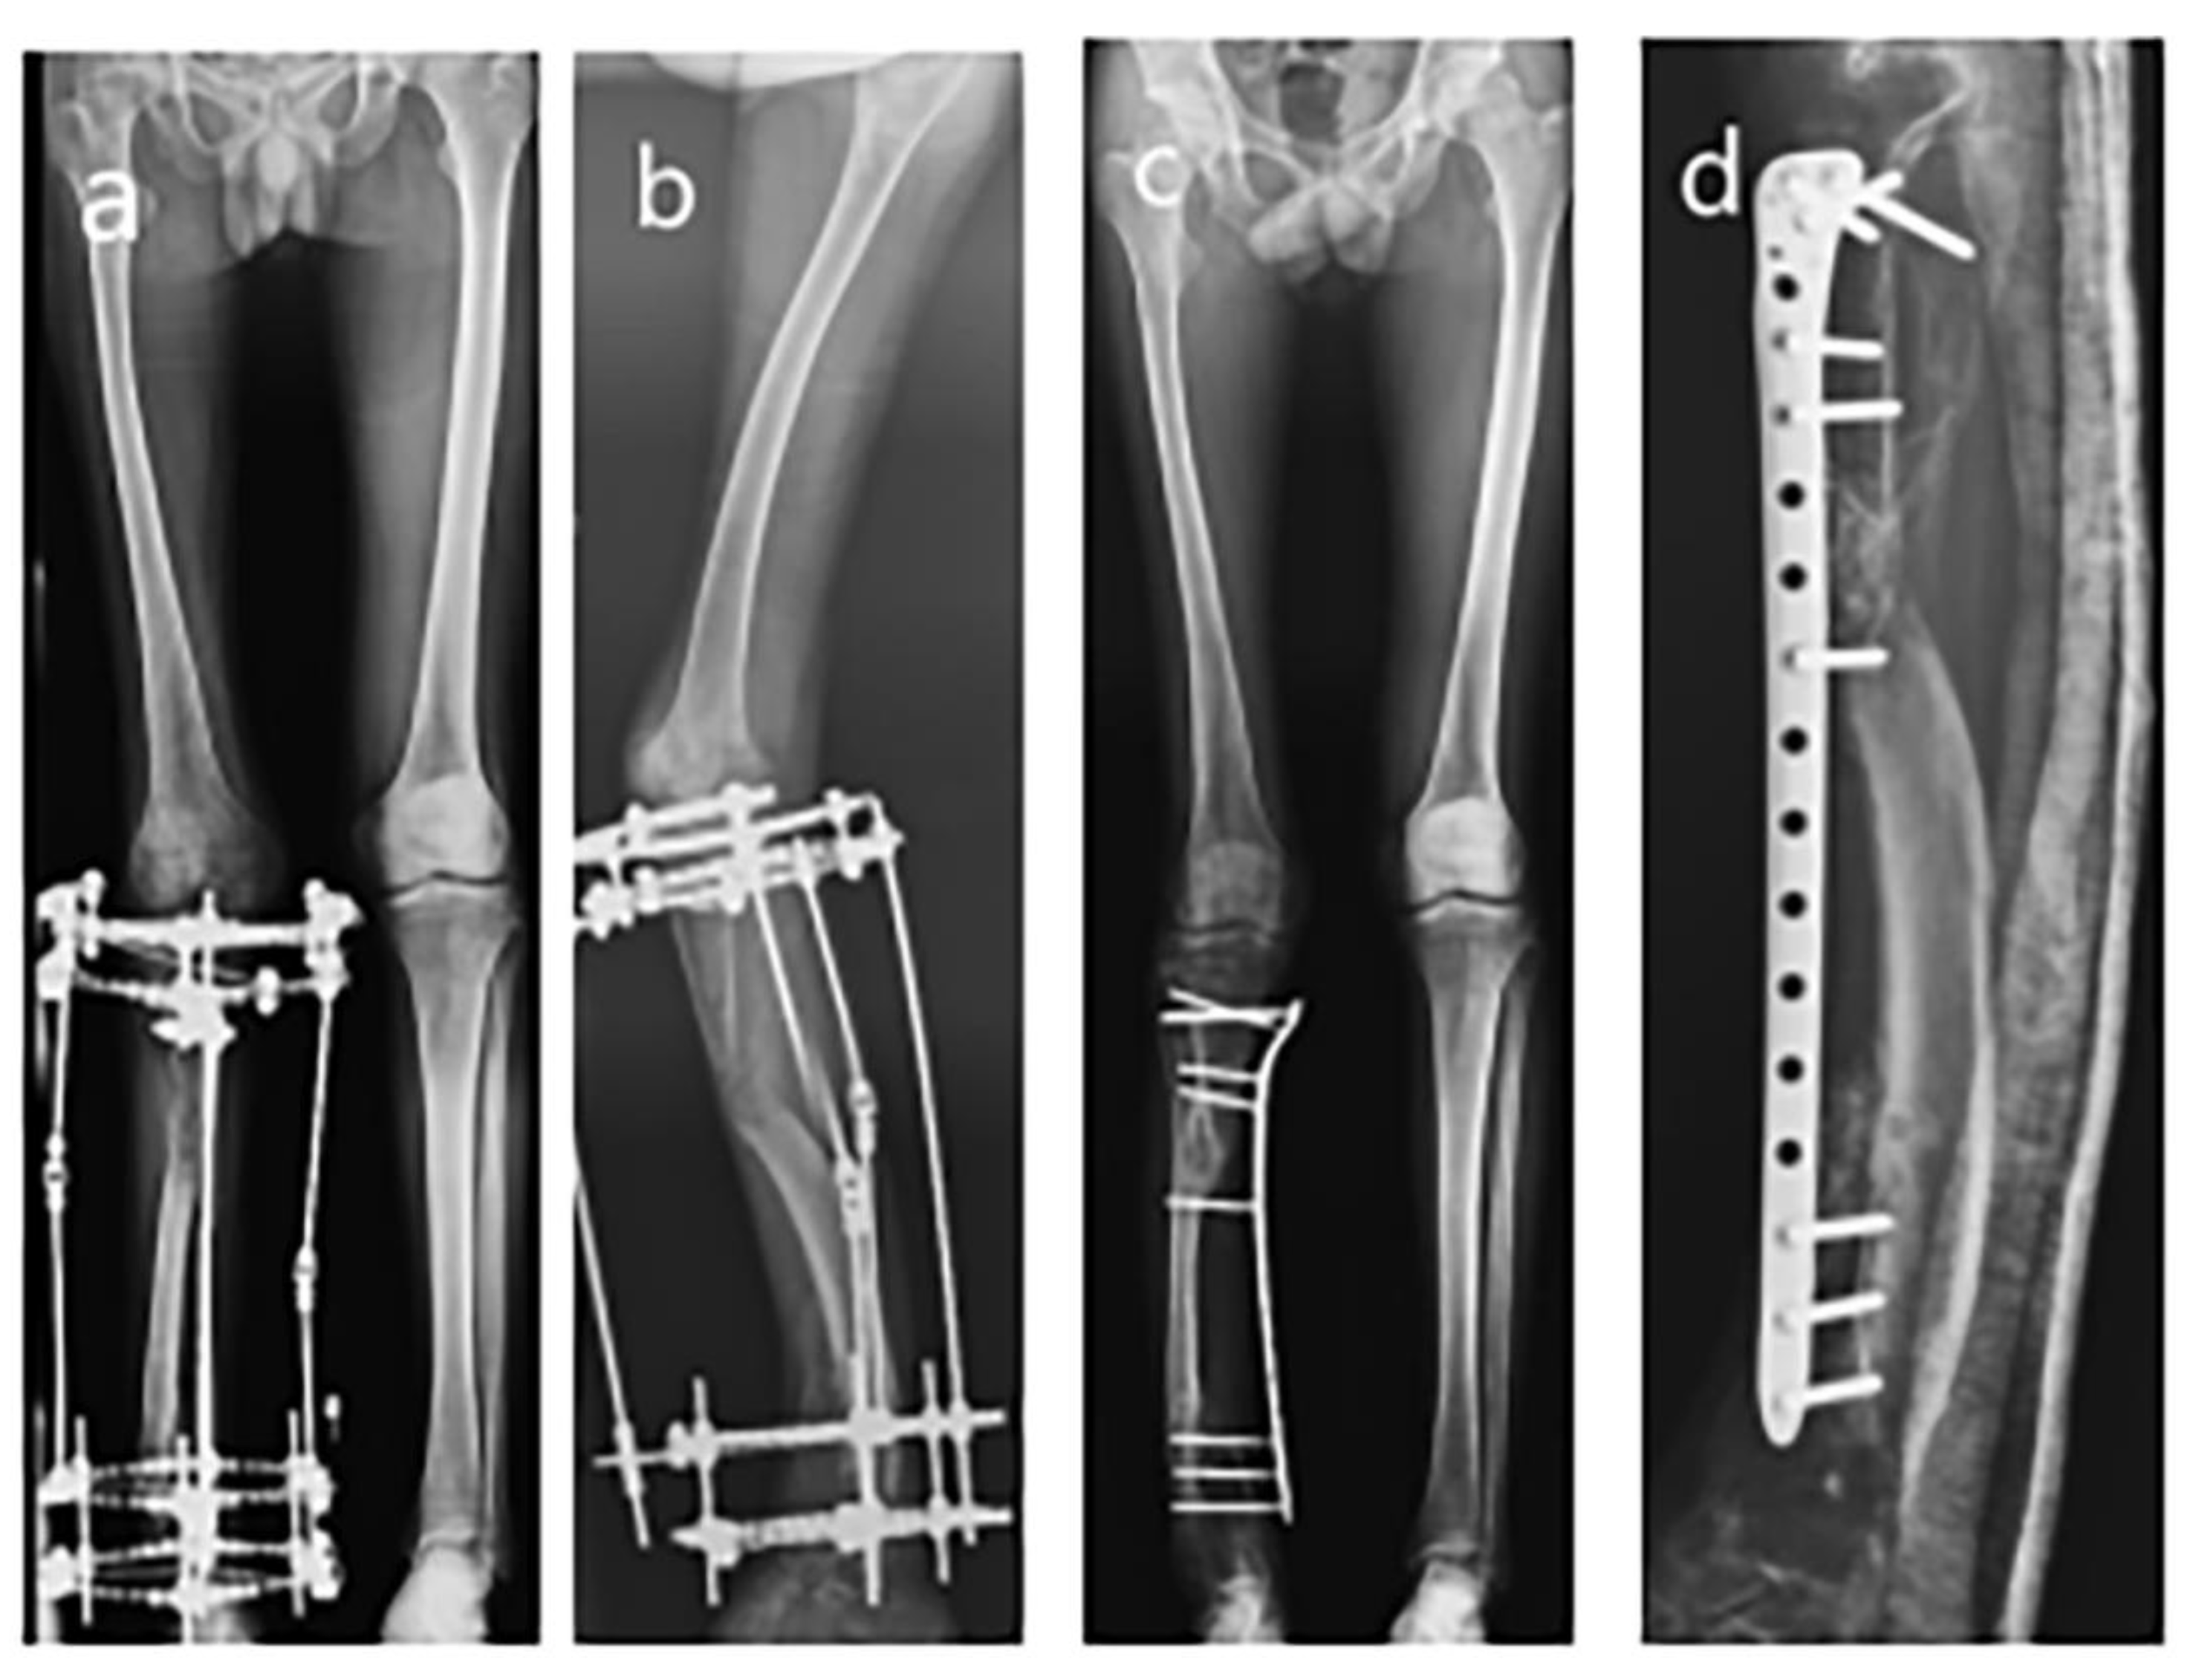

Figure 2.

Series radiographs of the lower extremity after Ilizarov apparatus instalment. (a) AP view radiograph of 5th-month follow-up; (b) AP view radiograph of 8th-month follow-up; (c) AP view radiograph of 9th-month follow-up; (d) Lateral view radiograph of 10th-month follow-up; (e) Lateral view radiograph of 5th-month follow-up; (f) Lateral view radiograph of 8th-month follow-up; (g) Lateral view radiograph of 9th-month follow-up; (h) Lateral view radiograph of 10th-month follow-up.